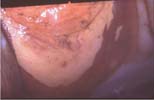

2) la colposcopie : le siège de l’adénose est le 1/3 supérieur  du vagin préférentiellement dans les culs de sacs antérieur et postérieur. Elle est rarement pure, c’est à dire retrouvée au stade du revêtement cylindrique. Dans la grande majorité des cas, elle est intéressée déjà par une transformation atypique de Grade I simple se traduisant par une vaste zone iodo-négative à contours nets au niveau du vagin. Cette transformation atypique de Grade I se traduit au début par une réaction blanche à l’application d’acide acétique et cette zone est toujours iodo-négative au test de SCHILLER. Comme dans le cas de la transformation atypique de Grade I, il faut surveiller la néo-jonction squamo-cylindrique qui peut à moment donné révéler un tableau de transformation atypique de Grade II débutante et nécessiter des biopsies de contrôle.